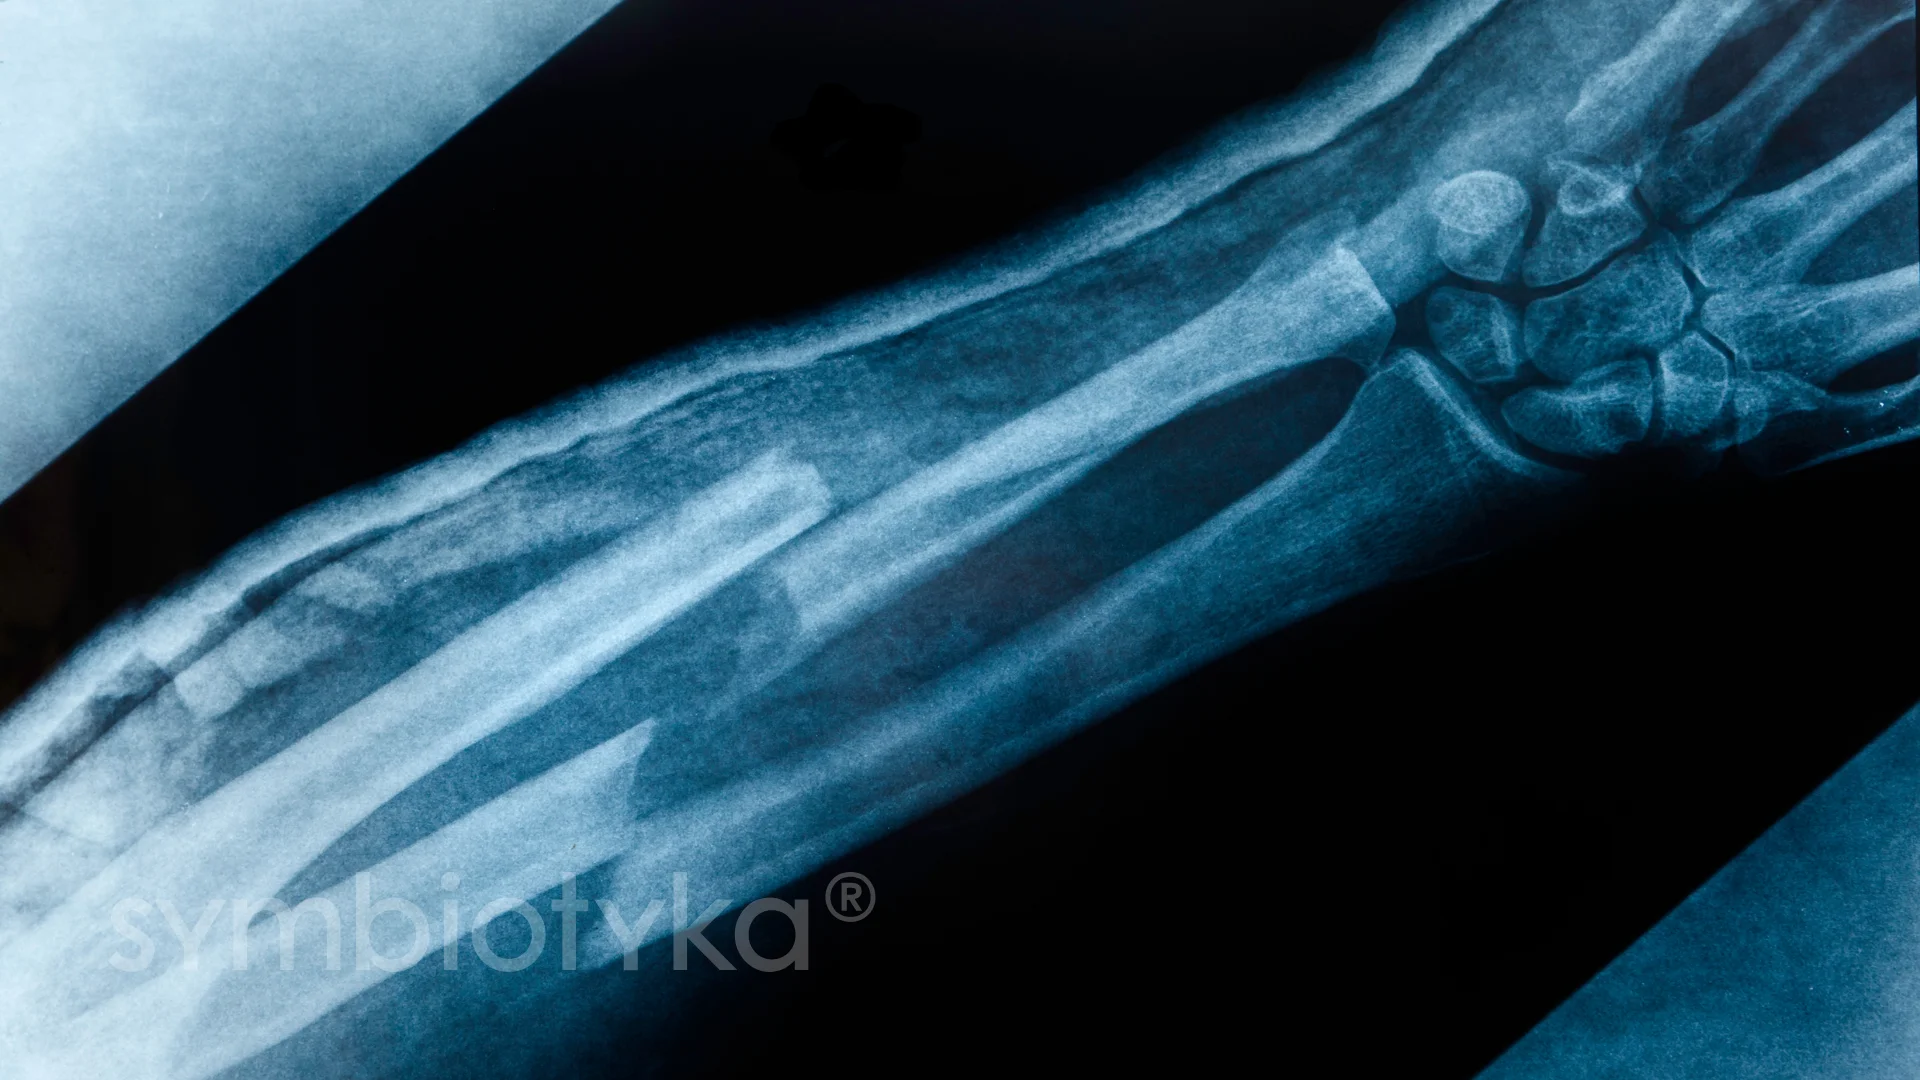

Як розробляти руку після перелому променевої кістки: поради для відновлення

Перелом променевої кістки — штука несмакотна, але, на жаль, часто зустрічається. Після такої травми важливо знати, як розробляти руку, щоб повернути їй колишню рухливість. Тут ми розглянемо основні етапи відновлення, поради фахівців і відповіді на часті запитання. Розмовлятимемо як на кухні за чаєм, але без нудятини.

Початковий етап відновлення

- Іммобілізація: Коли зняли гіпс, не думай, що можна одразу «рушати в бій». Тут процедур багато.